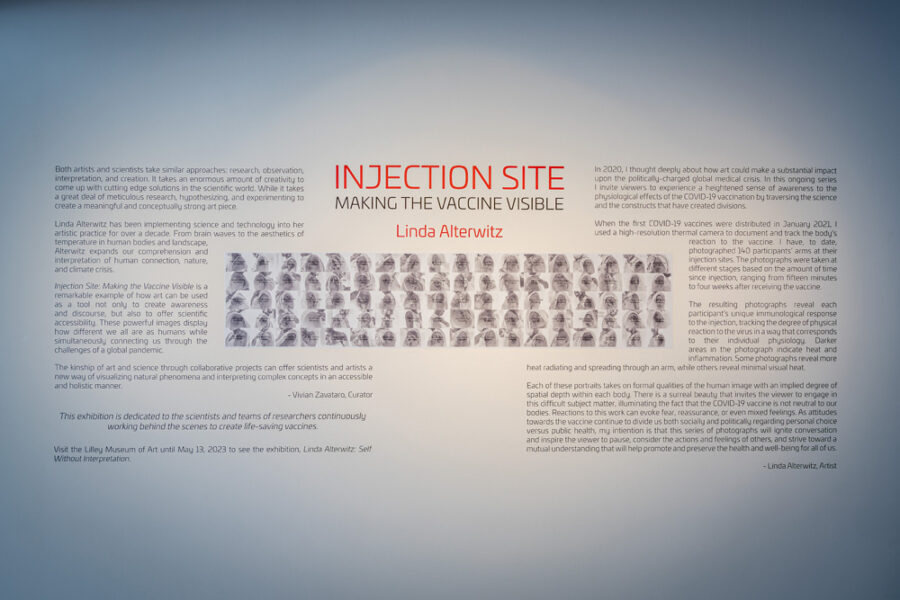

Injection Site addresses the politically charged global medical crisis of COVID-19. The project involved the use of a high-resolution thermal camera to photograph the arms of participants after vaccination. This has resulted in images over 130 participants, each image documenting and creating a visual trace of each person’s reaction to the vaccine. Rather than providing a simple scientific record, the ethereal images serve as evocative statements about individuality and our collective humanity. This project was intended to avoid being a polemic statement, but rather to cause pause for thought, to ignite conversation, and promote a mutual consideration for the actions and feeling of others, during a period when the health and wellbeing for all of us was such a contentious and divisive issue.

Although the memory of the COVID-19 pandemic may no longer sit at the forefront of our minds, beneath the surface it continues to stir fear, tension, and the pressure of what may still lie ahead — and for good reason. These feelings should not be ignored. We continue to live amid a perfect storm of global warming, overpopulation, habitat loss, and an increasing reliance on a digital world bring us ever closer to the next planetary threat. Despite the warning signs, we are not making the necessary changes to protect ourselves or our environment.